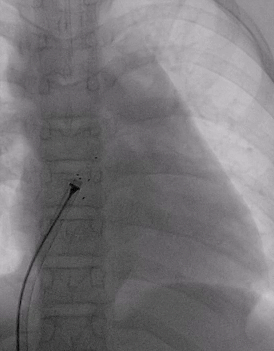

术前造影:室间隔缺损处造影,造影显示有膜部瘤形成,测量缺损大小,左侧基底大小10.8mm,右侧分流口2处,分流大小约2mm。

室间隔缺损介入封堵

根据术前测量和术中造影结果,选择MemoSorb全降解封堵器ABFDQ-Ⅱ08,配合8F可降解封堵器介入输送系统进行封堵。

建立输送轨道

飘导丝法导丝过室间隔缺损

圈套器抓捕导丝

送入8F输送鞘

改变输送鞘方向

使输送鞘朝向心尖

展开左右盘面

左盘展开

右盘展开并造影

基本无残余分流